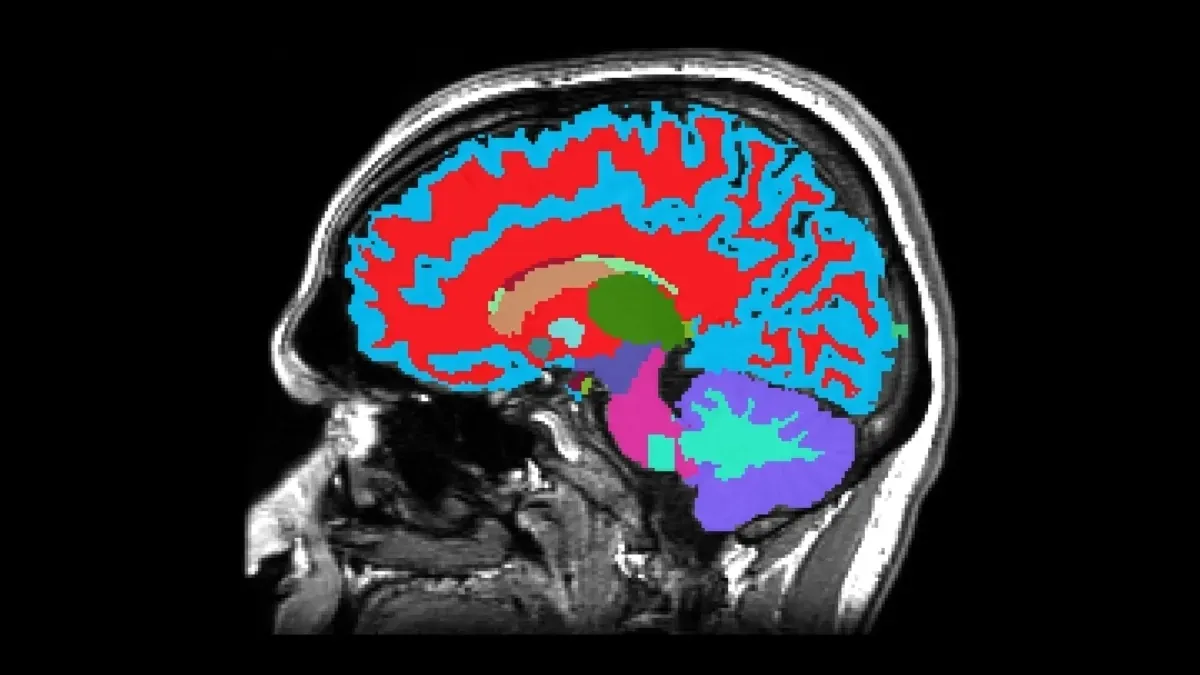

ابزار جدیدی که با استفاده از «تصویربرداری رزونانس مغناطیسی» (MRI: Magnetic Resonance Imaging) توسعه یافته، این امکان را فراهم میکند تا تنها از طریق یک تصویر مغزی، شاخصهایی مرتبط با پیری شناسایی شود. این مدل با بهرهگیری از الگوریتمهای «یادگیری ماشین» (machine learning) میتواند سرعت پیری یک فرد را بر اساس ویژگیهای ساختاری مغز، از جمله حجم ماده خاکستری، ضخامت قشر مغز (cortex) و سلامت «هیپوکامپ» (hippocampus)، برآورد کند.

هیپوکامپ که نقشی کلیدی در حافظه و یادگیری دارد، یکی از نخستین مناطقی است که در بیماریهای نورودژنراتیو مانند «آلزایمر» (Alzheimer's disease) دچار تحلیل میشود. کاهش زودهنگام در اندازه این بخش از مغز، حتی پیش از بروز اختلالات شناختی آشکار، میتواند نشانهای از تسریع در روند پیری عصبی باشد. این کشف به پژوهشگران اجازه داده تا به جای واکنش به بیماری در مراحل پیشرفته، به پیشبینی و پیشگیری بپردازند.